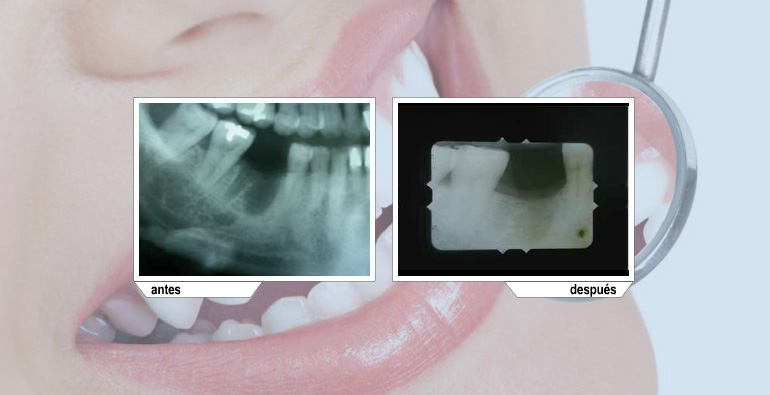

En los casos de pérdida dental la mejor restauración que podemos ofrecer es por medio de implantes dentales. Siempre se deberá contar con la mejor tecnología para minimizar el margen de error.

Ya sea inmediato a una extracción o en un defecto óseo ya establecido, este tratamiento nos ayuda a volver a tener suficiente cantidad de hueso para la colocación de implantes.